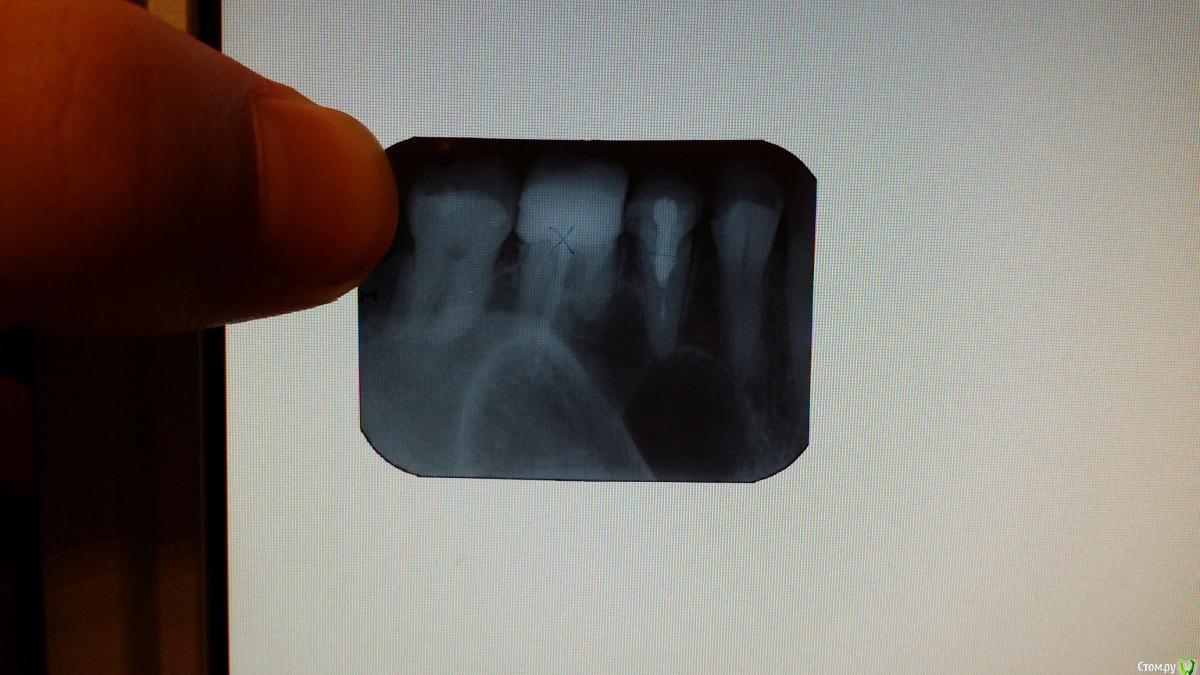

natali777 Опубликовано 6 января, 2016 Автор Поделиться Опубликовано 6 января, 2016 в день удаления Ссылка на комментарий